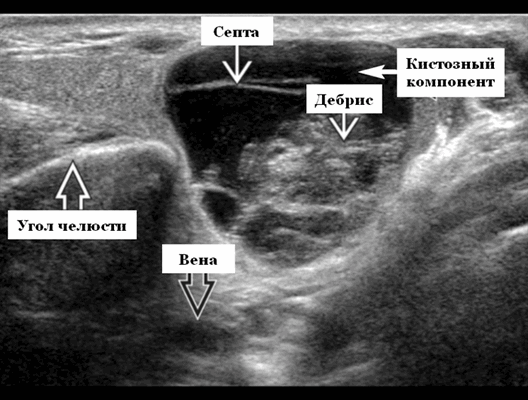

Ультразвуковая визуализация. Общие особенности. Лучший диагностический признак на УЗИ слюнной железы - резко окаймленные, гетерогенные образования околоушного хвоста ± кистозные компоненты. Расположение. Интрапаротидное, чаще, чем периаротидое или верхние шейные лимфатическое узлы. Чаще всего в пределах околоушного хвоста поверхностно от угла нижней челюсти

Результаты ультразвукового исследования слюнных желез

- Серошкальное УЗИ дает специфичность 91%, точность 89%. Большая опухоль Вартина клинически очевидна. При ультразвуковом исследовании четко выраженная гипоэхогенная некальцинированная опухоль в верхушке поверхностной доли околоушной железы. Гетерогенная внутренняя архитектура с кистозными и солидными компонентами. Мультисептированное кистозное поражение с толстыми стенками и детритом ± заднее усиление. Имеет тенденцию оставаться эллиптической или почковидной формы даже при больших размерах. Маленькая опухоль Вартина: случайная находка. Небольшая, эллиптическая, плотная почковидная масса в известном месте внутрипаротидного лимфатического узла. Гетерогенная архитектура и эхогенные ворота. Имитирует внешний вид лимфатического узла. Множественность поражений, односторонних или двусторонних (20%). На УЗИ нет инфильтрации кожи или подкожной ткани

- Цветной допплер: видные внутропухолевые (при небольших солидных опухолях) и перегородочные (могут поражать) сосуды.